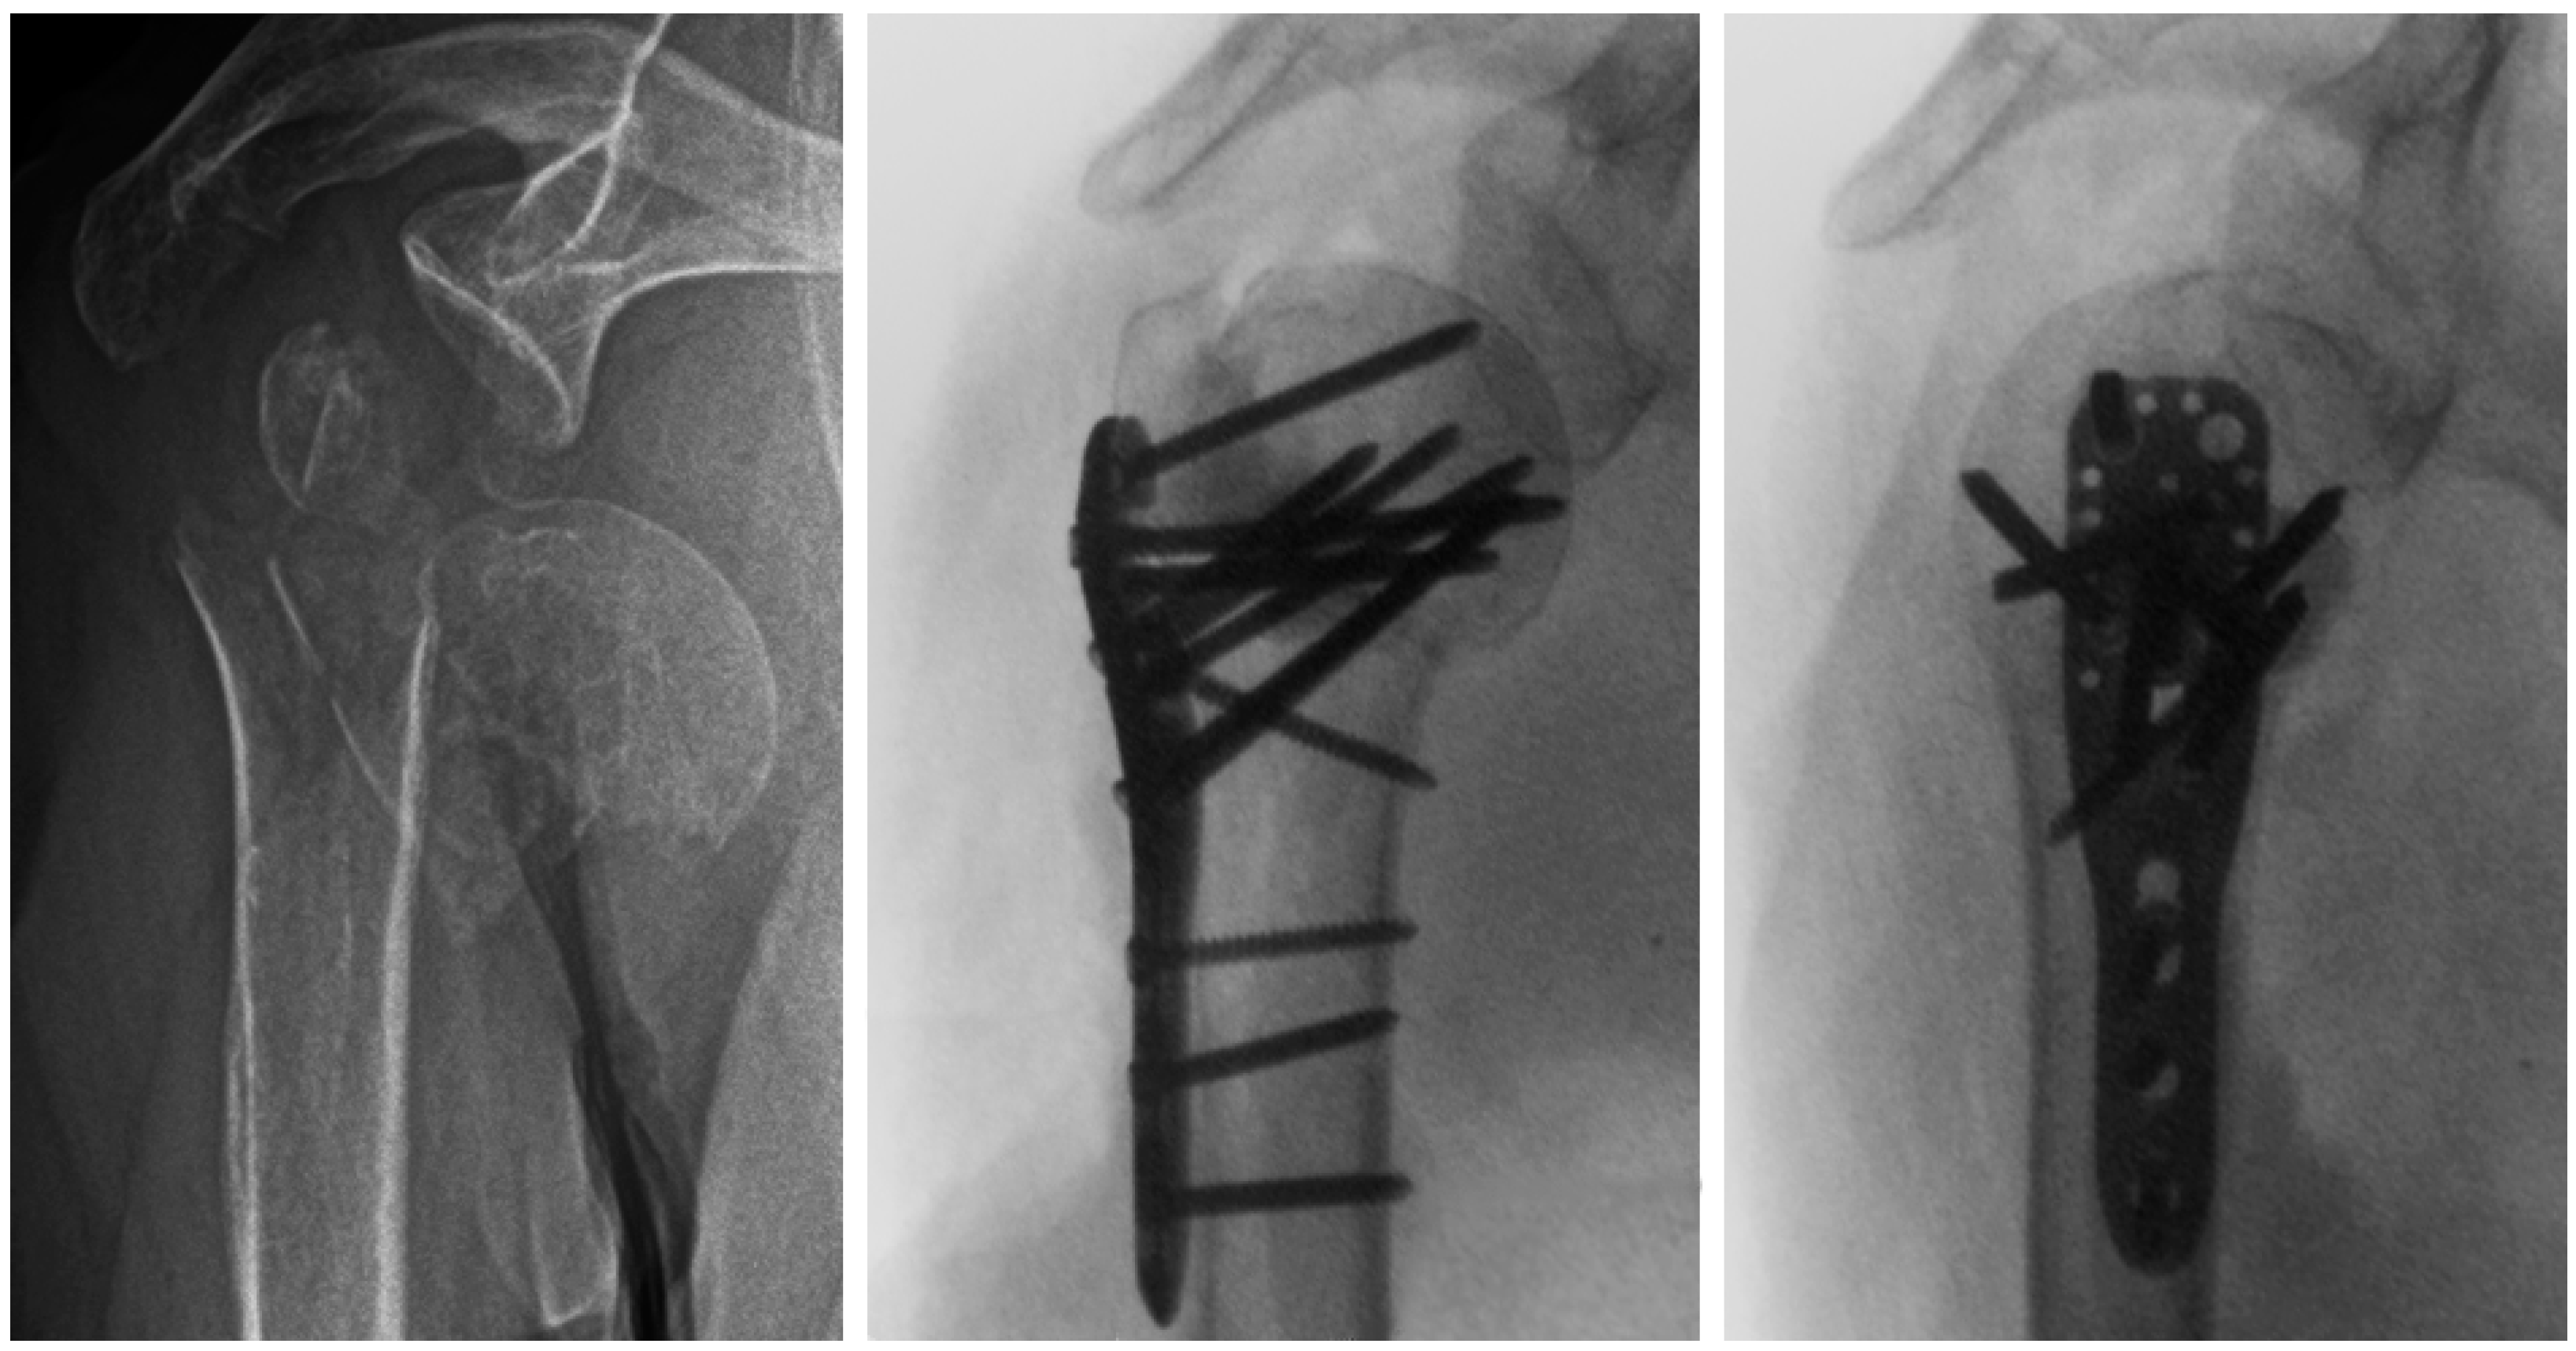

- Hristov, S.; Visscher, L.; Winkler, J.; Zhelev, D.; Ivanov, S.; Veselinov, D.; Baltov, A.; Varga, P.; Berk, T.; Stoffel, K.; et al. A Novel Technique for Treatment of Metaphyseal Voids in Proximal Humerus Fractures in Elderly Patients. Medicina 2022, 58, 1424. [Google Scholar] [CrossRef] [PubMed]